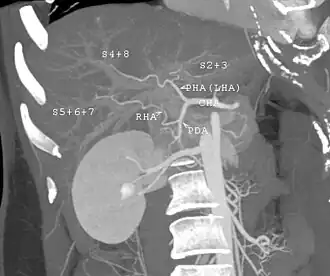

CT scan performed for evaluation of a potential donor. The image shows an unusual variation of the hepatic artery. The left hepatic artery supplies not only the left lobe but also segment 8. The anatomy makes right lobe donation impossible. Even used as left lobe or lateral segment donation, it would be very technically challenging in anastomosing the small arteries.

Any member of the family, parent, sibling, child, spouse, or a volunteer can donate their liver. The criteria[18][19] For a liver donation, include: